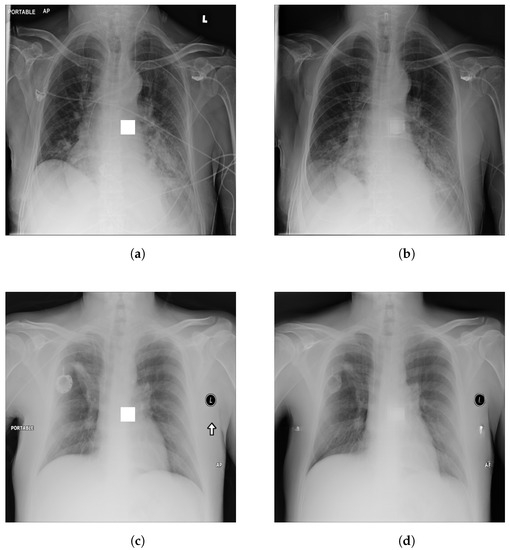

4.1. -LDP-Processed CXR Images

4.2. Qualitative Assessment of LDP-Processed CXR Images